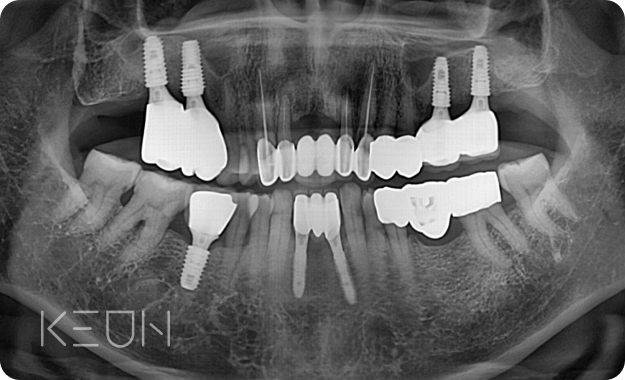

뼈이식 임플란트 전후사진.

- After

- Before

*모든 치료전/후 사진은 환자분의 동의하에 촬영 및 게시되었습니다.